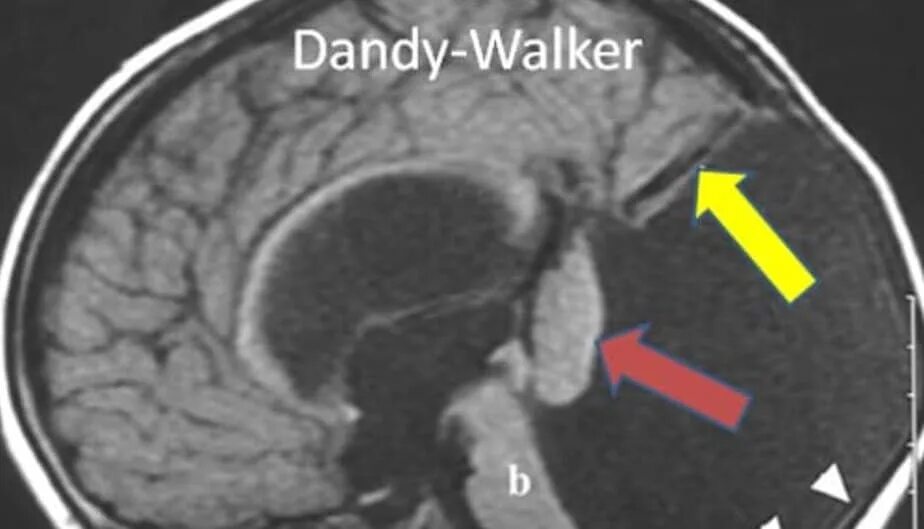

Денди уокера мрт